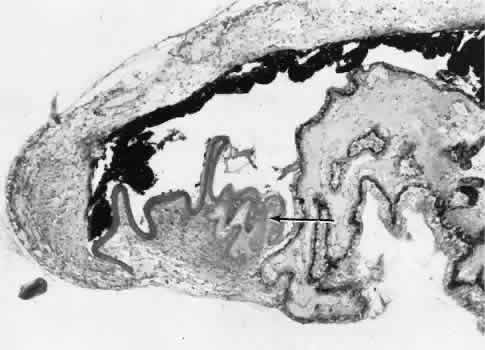

Wound healing of the posterior uveal tract follows the general principles for healing of vascularized tissue. The iris, however, heals differently. When the iris wound is perpendicular to its circumferential ridges, such as in a typical peripheral iridectomy or iridotomy, the cut edges pull apart. Granulation tissue does not form to close iridectomy incisions probably because of the inhibitory effect of the aqueous flowing through the opening of these small incisions. Iridotomies created by argon laser (Fig. 10) may be anatomically closed by apparent migration of iris pigment epithelium.36,37

Fig. 10. Scanning electron micrograph of the posterior surface of the iris in a case of angle closure glaucoma treated with argon laser iridotomy. Centrally, there are three areas of penetration of iris tissue. Iris pigment epithelium has been lost for a considerable distance from the actual opening (arrow). Normal iris pigment epithelium is present peripherally.